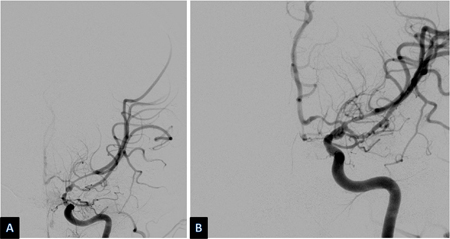

Vasospasm develops between days 4 and 14 after SAH and is seen on angiography in 50% to 70% of cases. Half of these patients develop delayed cerebral ischemia (DCI) secondary to reduced regional or overall cerebral blood flow (CBF).[190] If untreated, DCI progresses to permanent cerebral infarction in 50% of cases. Ischemic deficits may also be seen in the absence of discrete angiographic vasospasm. This is believed to be due, in part, to altered autoregulation of distal cerebral vessels, microthrombi in such vessels, and/or cortical spreading depolarization.[191] Risk factors for DCI are a poor clinical condition on admission, quantity and duration of exposure to subarachnoid blood, thick blood collections in cisterns and fissures, intraventricular blood, and duration of unconsciousness.[172][177][192][193][194][195] Although the presence of blood in the subarachnoid space is necessary to the development of vasospasm, surgical clipping, during which most of the subarachnoid blood is washed out, does not seem to carry a lesser risk of vasospasm than endovascular coiling.[196][197][Figure caption and citation for the preceding image starts]: Severe vasospasm of distal left internal carotid artery and proximal middle and anterior cerebral arteries before (A) and after (B) intra-arterial infusion of nicardipine and transluminal balloon angioplastyCourtesy of Dr Salah Keyrouz; used with permission [Citation ends].Severe vasospasm of distal left internal carotid artery and proximal middle and anterior cerebral arteries before (A) and after (B) intra-arterial infusion of nicardipine and transluminal balloon angioplasty[Figure caption and citation for the preceding image starts]: Left frontal infarct (arrows) in a patient with subarachnoid hemorrhage-related vasospasmCourtesy of Dr Salah Keyrouz; used with permission [Citation ends].Left frontal infarct (arrows) in a patient with subarachnoid hemorrhage-related vasospasm